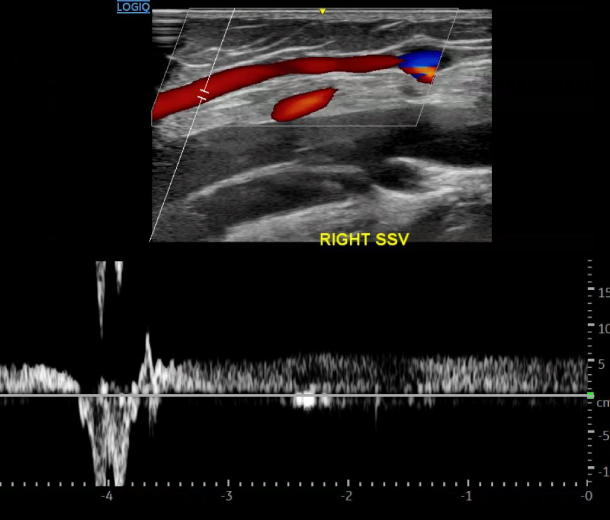

도플러 초음파 검사

해부학적 정보와 함께 혈관의 기형, 혈류의 흐름까지 동시에 컬러로 확인할 수 있는 전문 초음파 검사입니다. 이 검사만으로도 간단하게 하지정맥류의 정확한 원인을 알 수 있습니다.